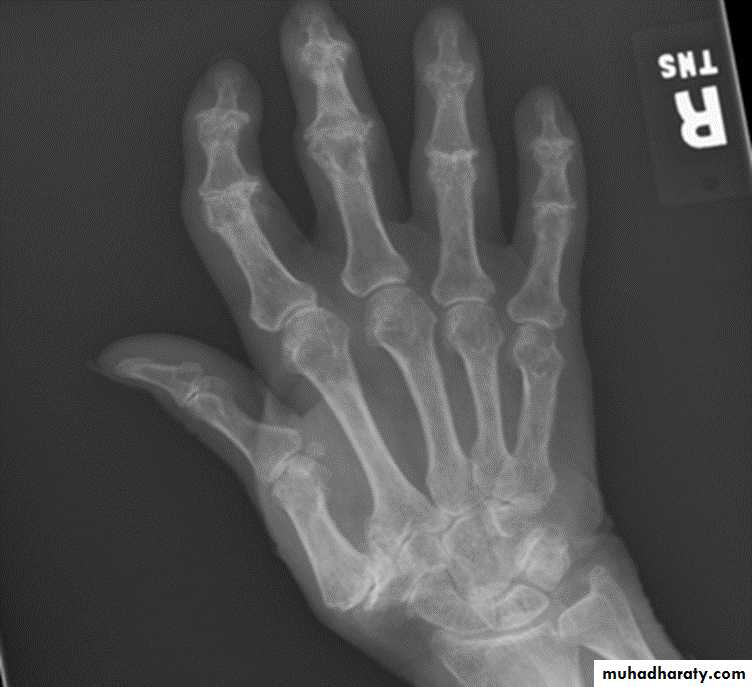

RHEUMATOID ARTHRITIS

Female:male = 3:l

Radiographic features:Early changes

* Peri articular soft tissue swelling (edema, synovial congestion)

*Peri articular osteoporosis in symmetrical distribution (hallmark)

* Preferred sites of early involvement

Hands: 2nd and 3rd MCP joint

Feet: 4th and 5th MTP joint

Late changes

*Erosions (pannus formation, granulation tissue) first attack joint portions in which protective cartilage is absent (i.e., capsular insertion site).

* Erosions of the ulnar styloid and triquetrum are characteristic.

* Subchondral cysts formation results from synovial fluid, which is pressed into bone marrow through destroyed cartilage.

Subluxations , Carpal instability and ulnar deviation .

* Fibrous ankylosis is a late finding.

Rheumatoid arthritis. Bilateral changes are fairly symmetrical. Soft-tissue swelling is demonstrated, especially over the ulnar styloids. Erosions are demonstrated at the carpus, distal radius and ulna, with joint space narrowing and collapse of bone. Metacarpophalangeal erosions are also seen associated with joint space narrowing. There is a swan-neck deformity of the right fifth distal interphalangeal joint

Gross rheumatoid arthritis at the carpus with ulnar deviation,

subluxation and joint narrowing at the metacarpophalangeal joints.Boutonniere deformities are present at the index and little fingers.